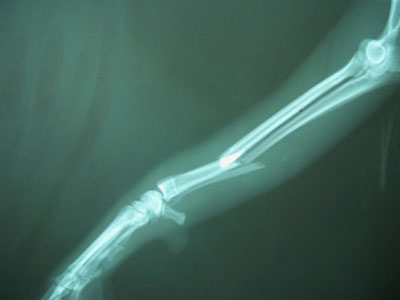

Πιντσεράκι 5,5 kg με 5ημερών τέλειο κάταγμα κάτω τρίτου διάφυσης αριστερής κερκίδας και ωλένης.